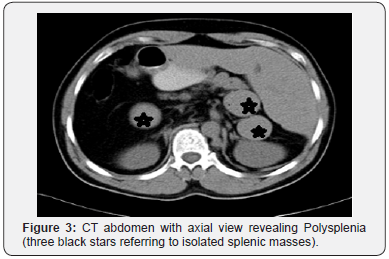

His general investigations (full blood count, random blood glucose, renal and liver profiles) were within normal ranges. His CXR showed normal lungs, levocardia and a right-sided gastric bubble. ECG revealed no abnormalities. A trans-thoracic echocardiography was normal apart from unusual drainage of hepatic veins directly into the right atrium. A multi-detector CT (MDCT) scan of the abdomen (with oral and intravenous contrast) confirmed the hiatus hernia (Figure 1) and revealed a right-sided stomach, a two-humped left-sided liver (Figure 2), polysplenia (three splenic masses, two on the left beneath the liver and one on the right) (Figure 3), a pre-pancreatic portal vein (Figure 4) and an absent inferior vena cava (IVC) with a direct continuation of azygous and hemi-azygous veins (Figure 5). Therefore, CT findings were consistent with heterotaxy syndrome with a left isomerism (polysplenia syndrome).

In view of his complaints; a laparoscopic repair of the hiatus hernia was planned. Following informed consent, he underwent a laparoscopic hernia repair. Patient was positioned in a supine position with both legs separated; Trendelenburg position with a 30-degree angle (but at certain steps a 45-degree position was adopted). Following pneumoperitoneum and during diagnostic laparoscopy, a few more findings were observed and deserved more attention; hepatic veins were draining directly into the right atrium and ductus venosus running from the left gastric vein into the right atrium. The small intestines were normally positioned. The pancreas was normal in both location and structure. Visualization of the esophageal hiatus was difficult as one splenic mass was lying in the lesser sac beneath the left lobe of liver obscuring hiatus hernia critical view (Figure 6).

The pattern of the associated anomalies depends on being a case of left or right isomerism. Right isomerism is consistent with asplenia, bilateral tri-lobed lungs, and more commonly cardiovascular anomalies, whereas left isomerism is associated with polysplenia, bilateral bi-lobed lungs and pancreatic anomalies with much lesser frequency of cardiac anomalies [1]. In fact, the occurrence of cardiac anomalies makes the patient susceptible to the development of congestive heart failure, so patients with right isomerism and asplenia have decreased survival compared to patients with left isomerism and polysplenia [1,3]. Multiple splenic nodules usually found along the greater curvature on the left or right sides [12]. In this reported case one splenic mass was lying beneath the left lobe of the liver and thus obscuring the critical view of the esophageal hiatus. Symptomatic polysplenia in adults is often caused by abnormal biliary and pancreatic duct drainage and small bowel obstruction [13], however, it was asymptomatic in this reported case. Interestingly, the pancreas was normal in position and structure in our patient, a finding that is reported in a similar report [3]. Nevertheless, literature has reported various pancreatic anomalies (short truncated pancreas, dorsal pancreas and pancreatic divism) that are associated with heterotaxy syndrome [1,12].